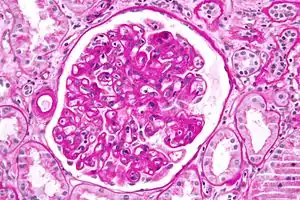

Diagnosis of acute rejection relies on clinical data—patient signs and symptoms but also calls on laboratory data such as blood or even tissue biopsy. The laboratory pathologist generally seeks three main histological signs: (1) infiltrating T cells, perhaps accompanied by infiltrating eosinophils, plasma cells, and neutrophils, particularly in telltale ratios, (2) structural compromise of tissue anatomy, varying by tissue type transplanted, and (3) injury to blood vessels. Tissue biopsy is restricted, however, by sampling limitations and risks/complications of the invasive procedure.[31][32][33] Cellular magnetic resonance imaging (MRI) of immune cells radiolabeled in vivo might—similarly to Gene Expression Profiling (GEP)—offer noninvasive testing.[34][35]